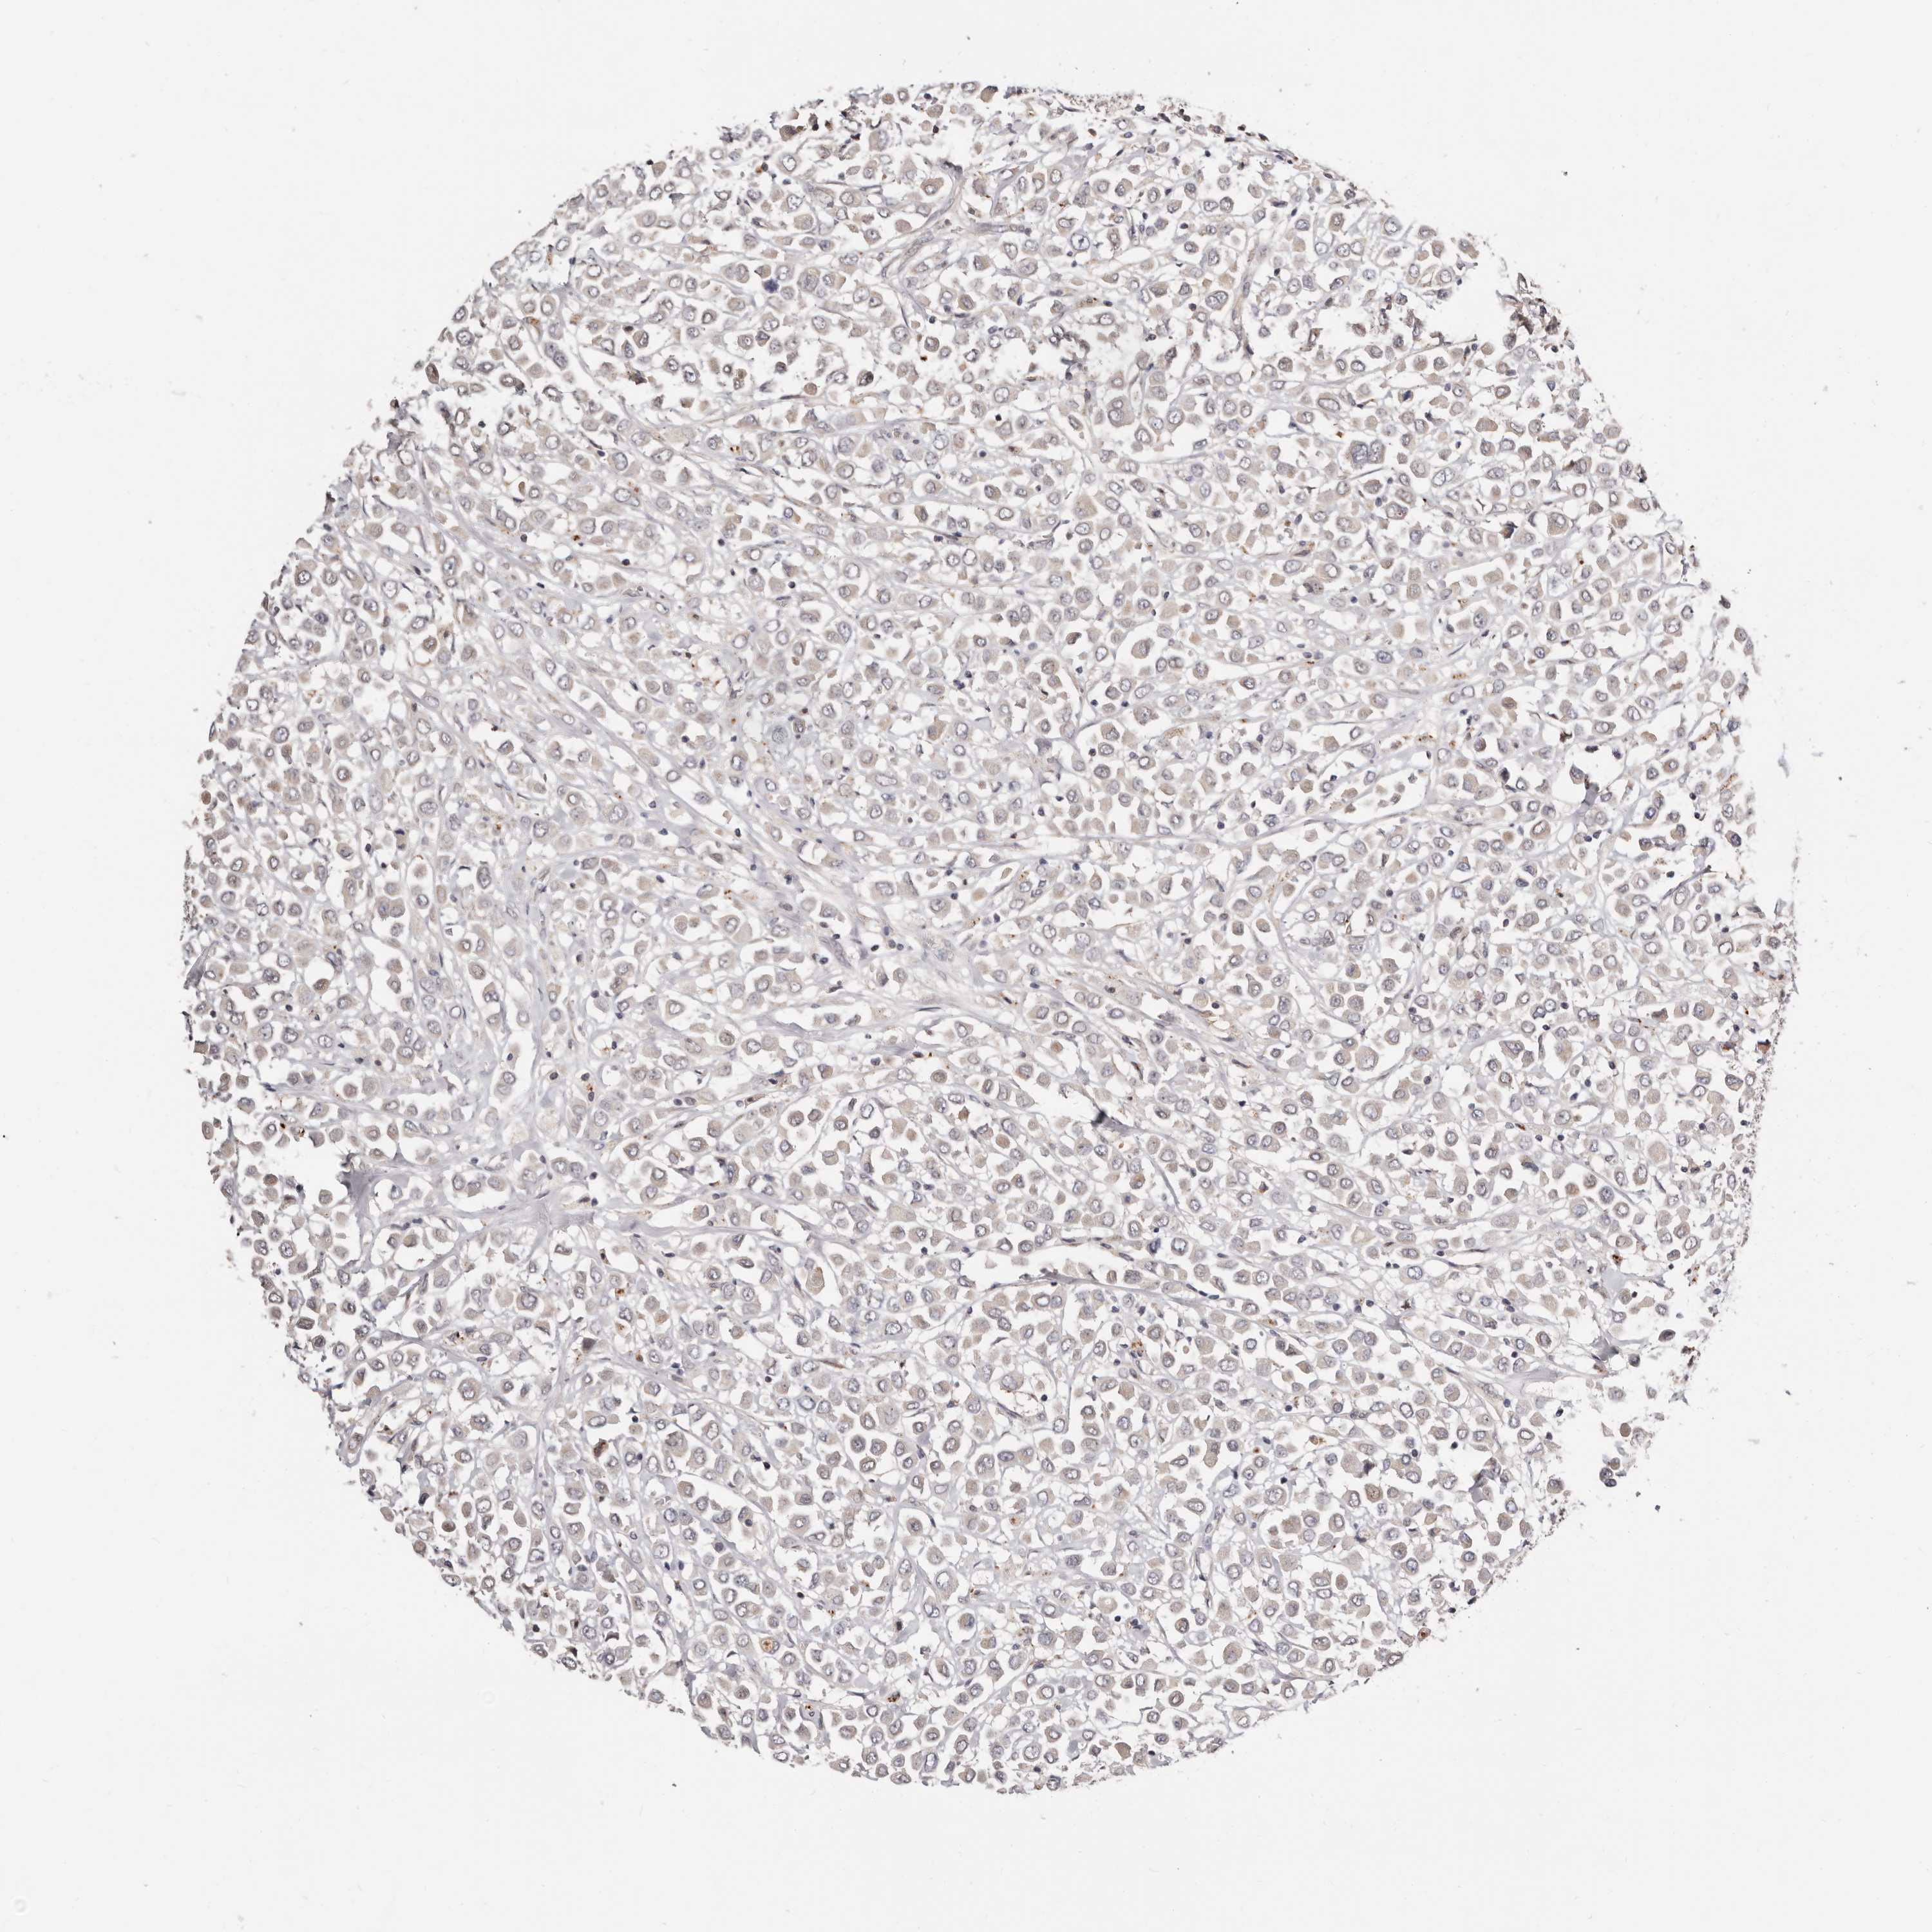

CANCER BREAST CANCER Show tissue menu

BRCA TCGA BRCA VALIDATION PROTEIN EXPRESSION

ANTIBODIES

AND

VALIDATION